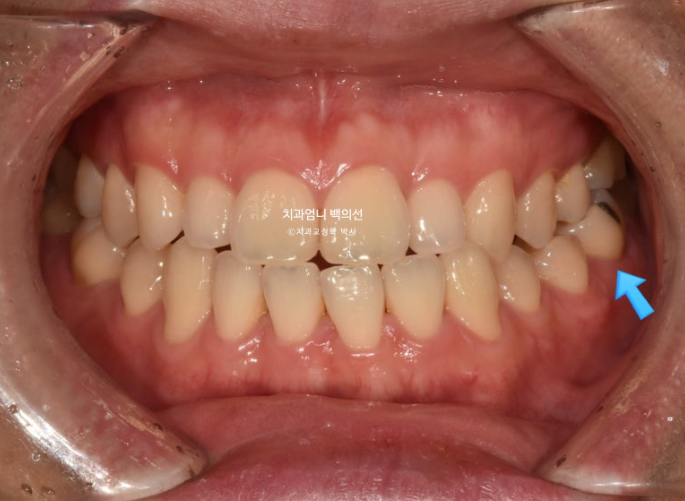

앞니 반대교합을 치료하러 오신 30대 후반의 환자분

파란화살표 작은어금니와 큰어금니가 반대교합입니다.

윗니가 아랫니를 덮지 못하는 반대교합과 절단교합이 보입니다.

어금니 교합은 3급입니다.

파란화살표 측절치는 정상보다 작습니다.

왜소치까지는 아니지만 작습니다.

작은 측절치 두 개를 라미네이트 등으로 사이즈를 키우면 윗니가 아랫니를 좀 더 확실하게 덮게끔 교합형성이 가능하지만 환자분은 원치 않으십니다.